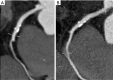

CT of a patient with normal coronary arteries who underwent cardiac computed tomography (CCT) with retrospective ECG-gated helical scan with ECG-controlled tube current modulation: multiplanar reconstructions of coronary arteries (A,B,C); indexed left ventricular function (D) and volume rendering (E).